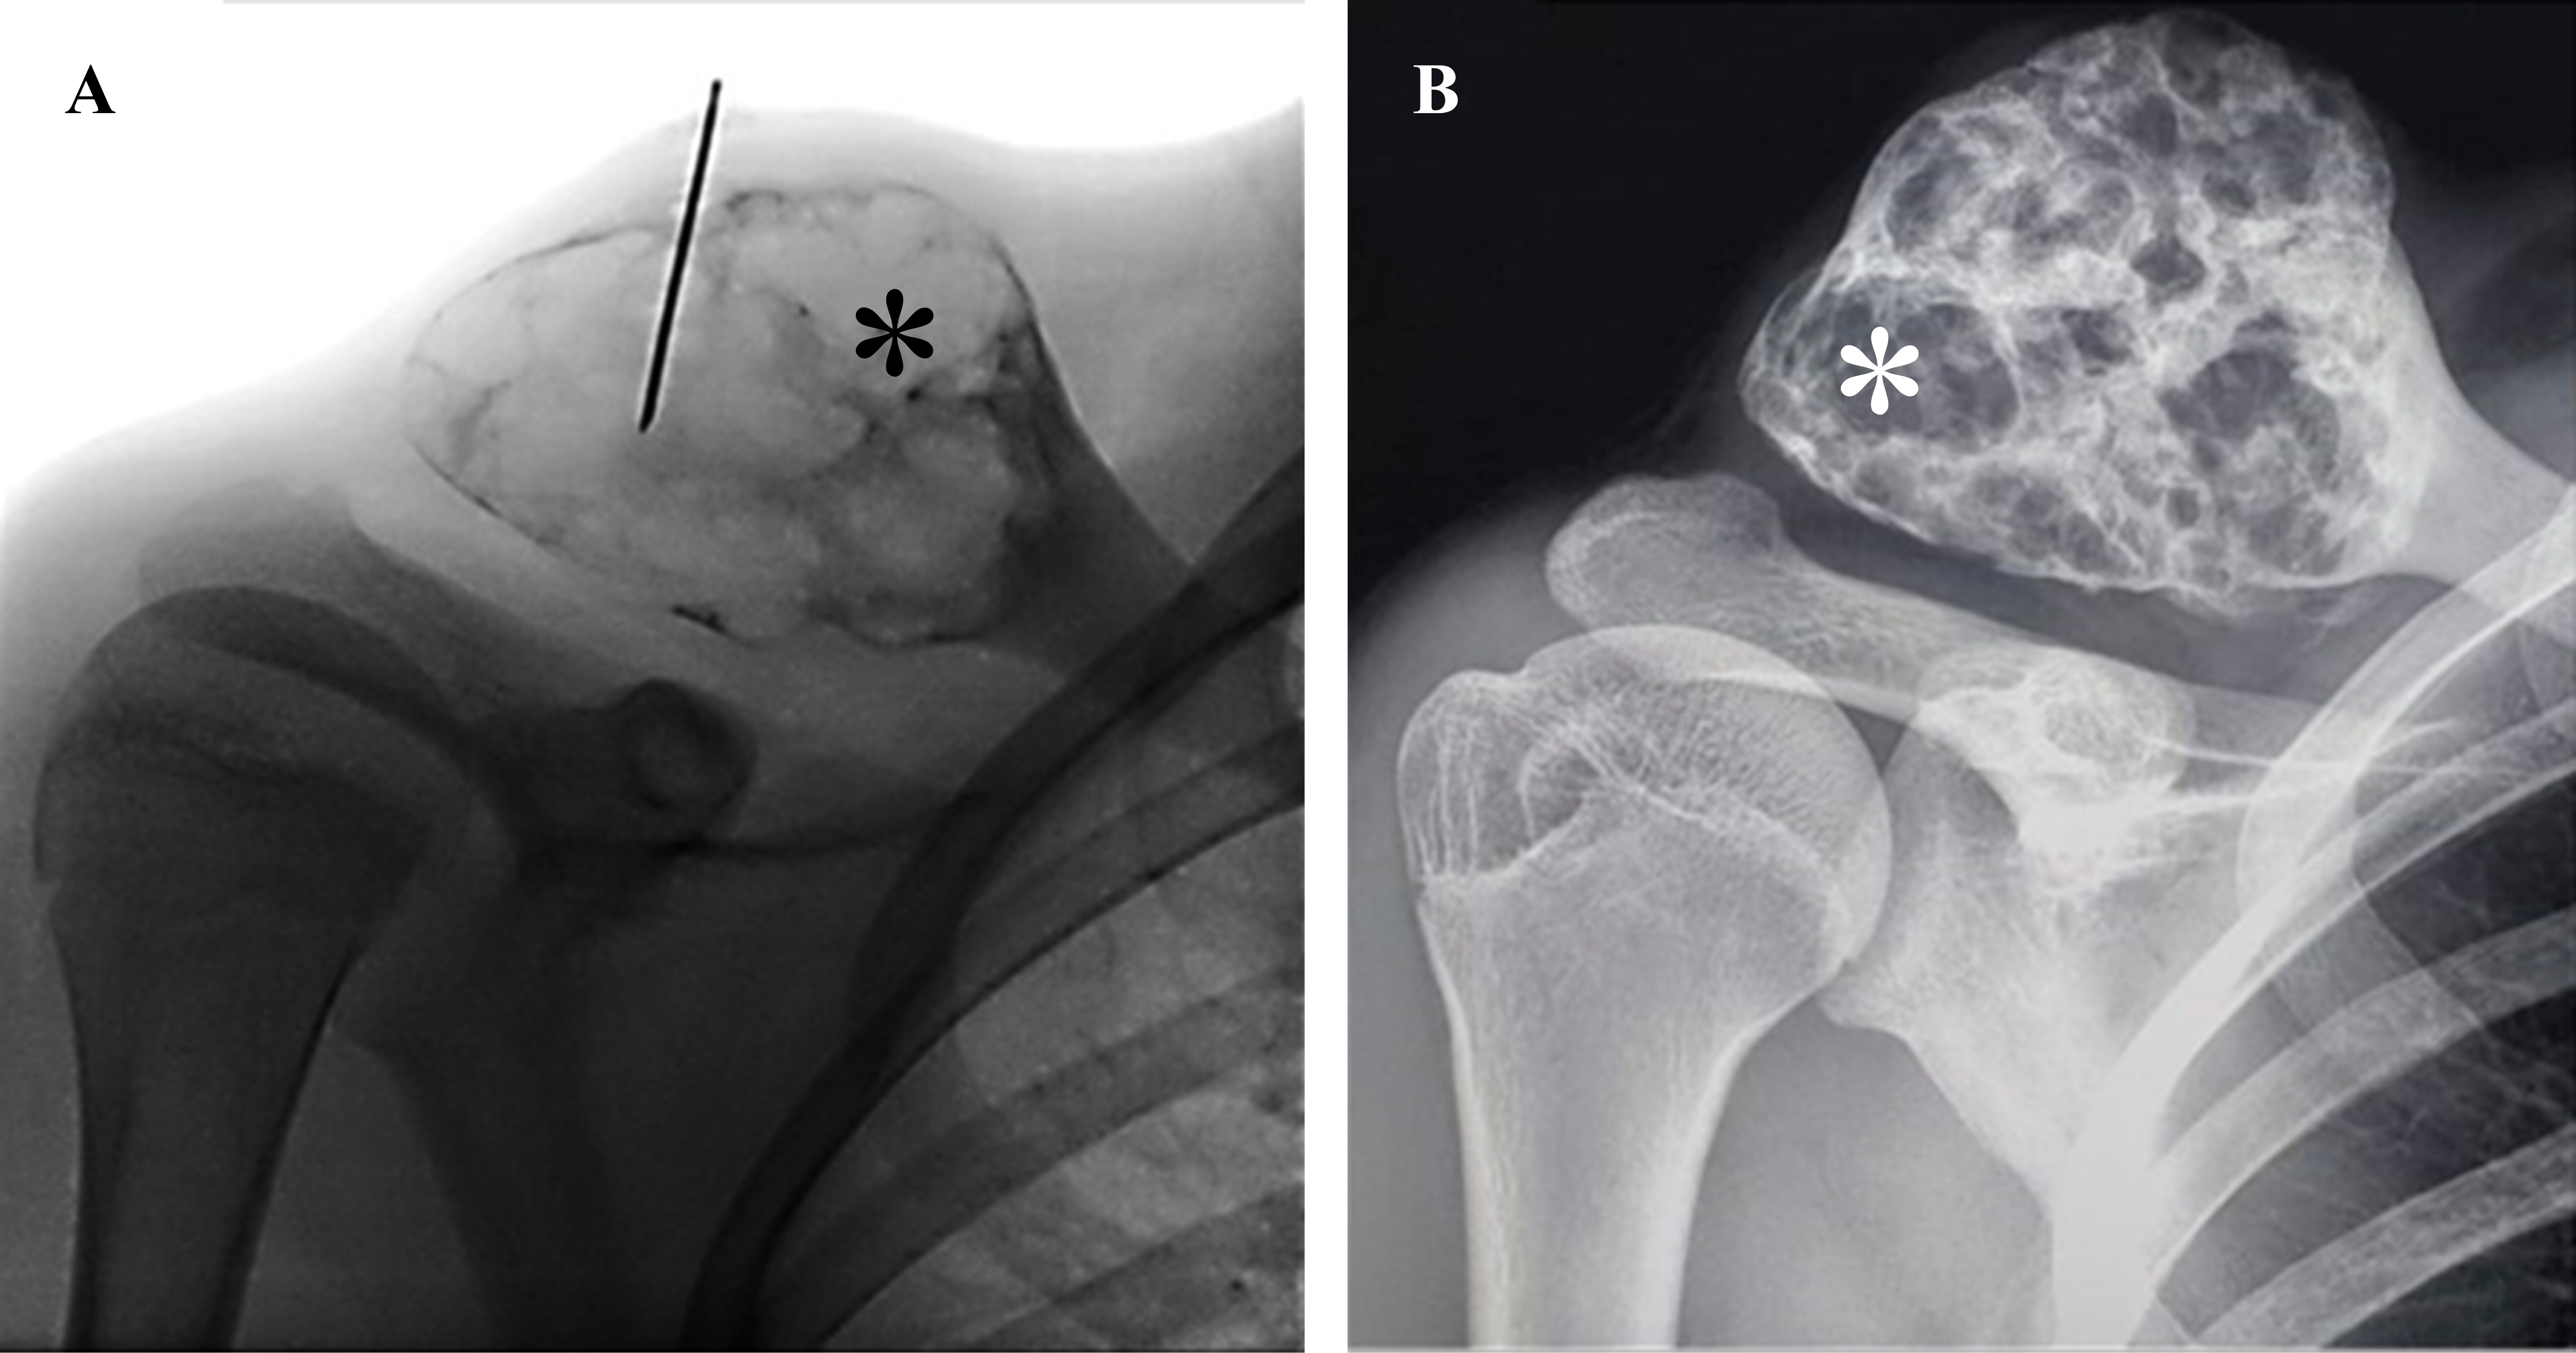

En los casos uno (Figura 1), cuatro, cinco, seis, siete y nueve se inyectaron 5 ml de polidocanol 3% en todas las sesiones. El primer paciente había recibido cirugía con curetaje óseo de la lesión un año antes por presentar recidiva del QOA, por lo que se optó por tratarle con escleroterapia. Al segundo paciente, en otra institución se le había realizado embolización de arterias aferentes del QOA, misma que fue inefectiva, motivo por el que se le realizó curetaje e injerto óseo; en menos de un año de seguimiento se evidenció recurrencia del QOA (Figura 2), razón por la cual se le indicó tratamiento con escleroterapia, recibió 5 ml de polidocanol 3% en la primera dosis y 10 ml en las dosis siguientes. En el tercero (Figura 3) y octavo pacientes se inyectaron 10 ml de la sustancia esclerosante en todas las sesiones. Número total de procedimientos: 44, cantidad de procedimientos por paciente: promedio 4.9 (DE: ± 2.0). Intervalo de dosis: promedio 11.54 semanas (DE: ± 14.57).

Figura 1